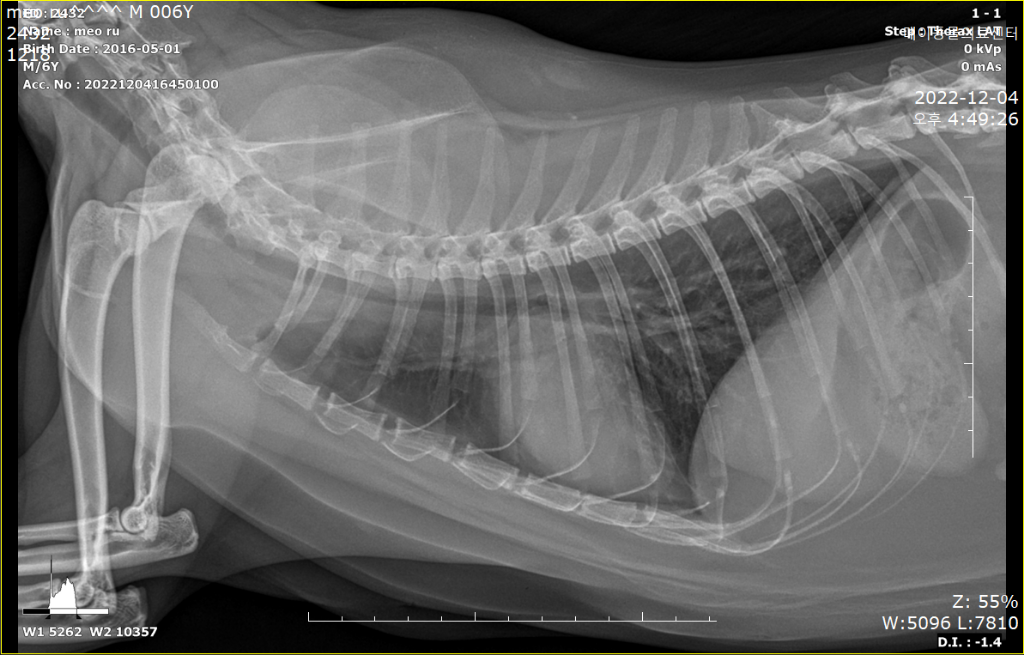

HCM이건 아니건간에 가슴쪽 엑스레이 사진에서 좌심방이 돌출하여 보이는 양상이 관찰되기 때문에

어떤 이유에서간 심장에 이상이 있을 가능성이 매우 높으니

환자의 증상에 따른 의학적 개입이 필요한 상황으로 생각됩니다.